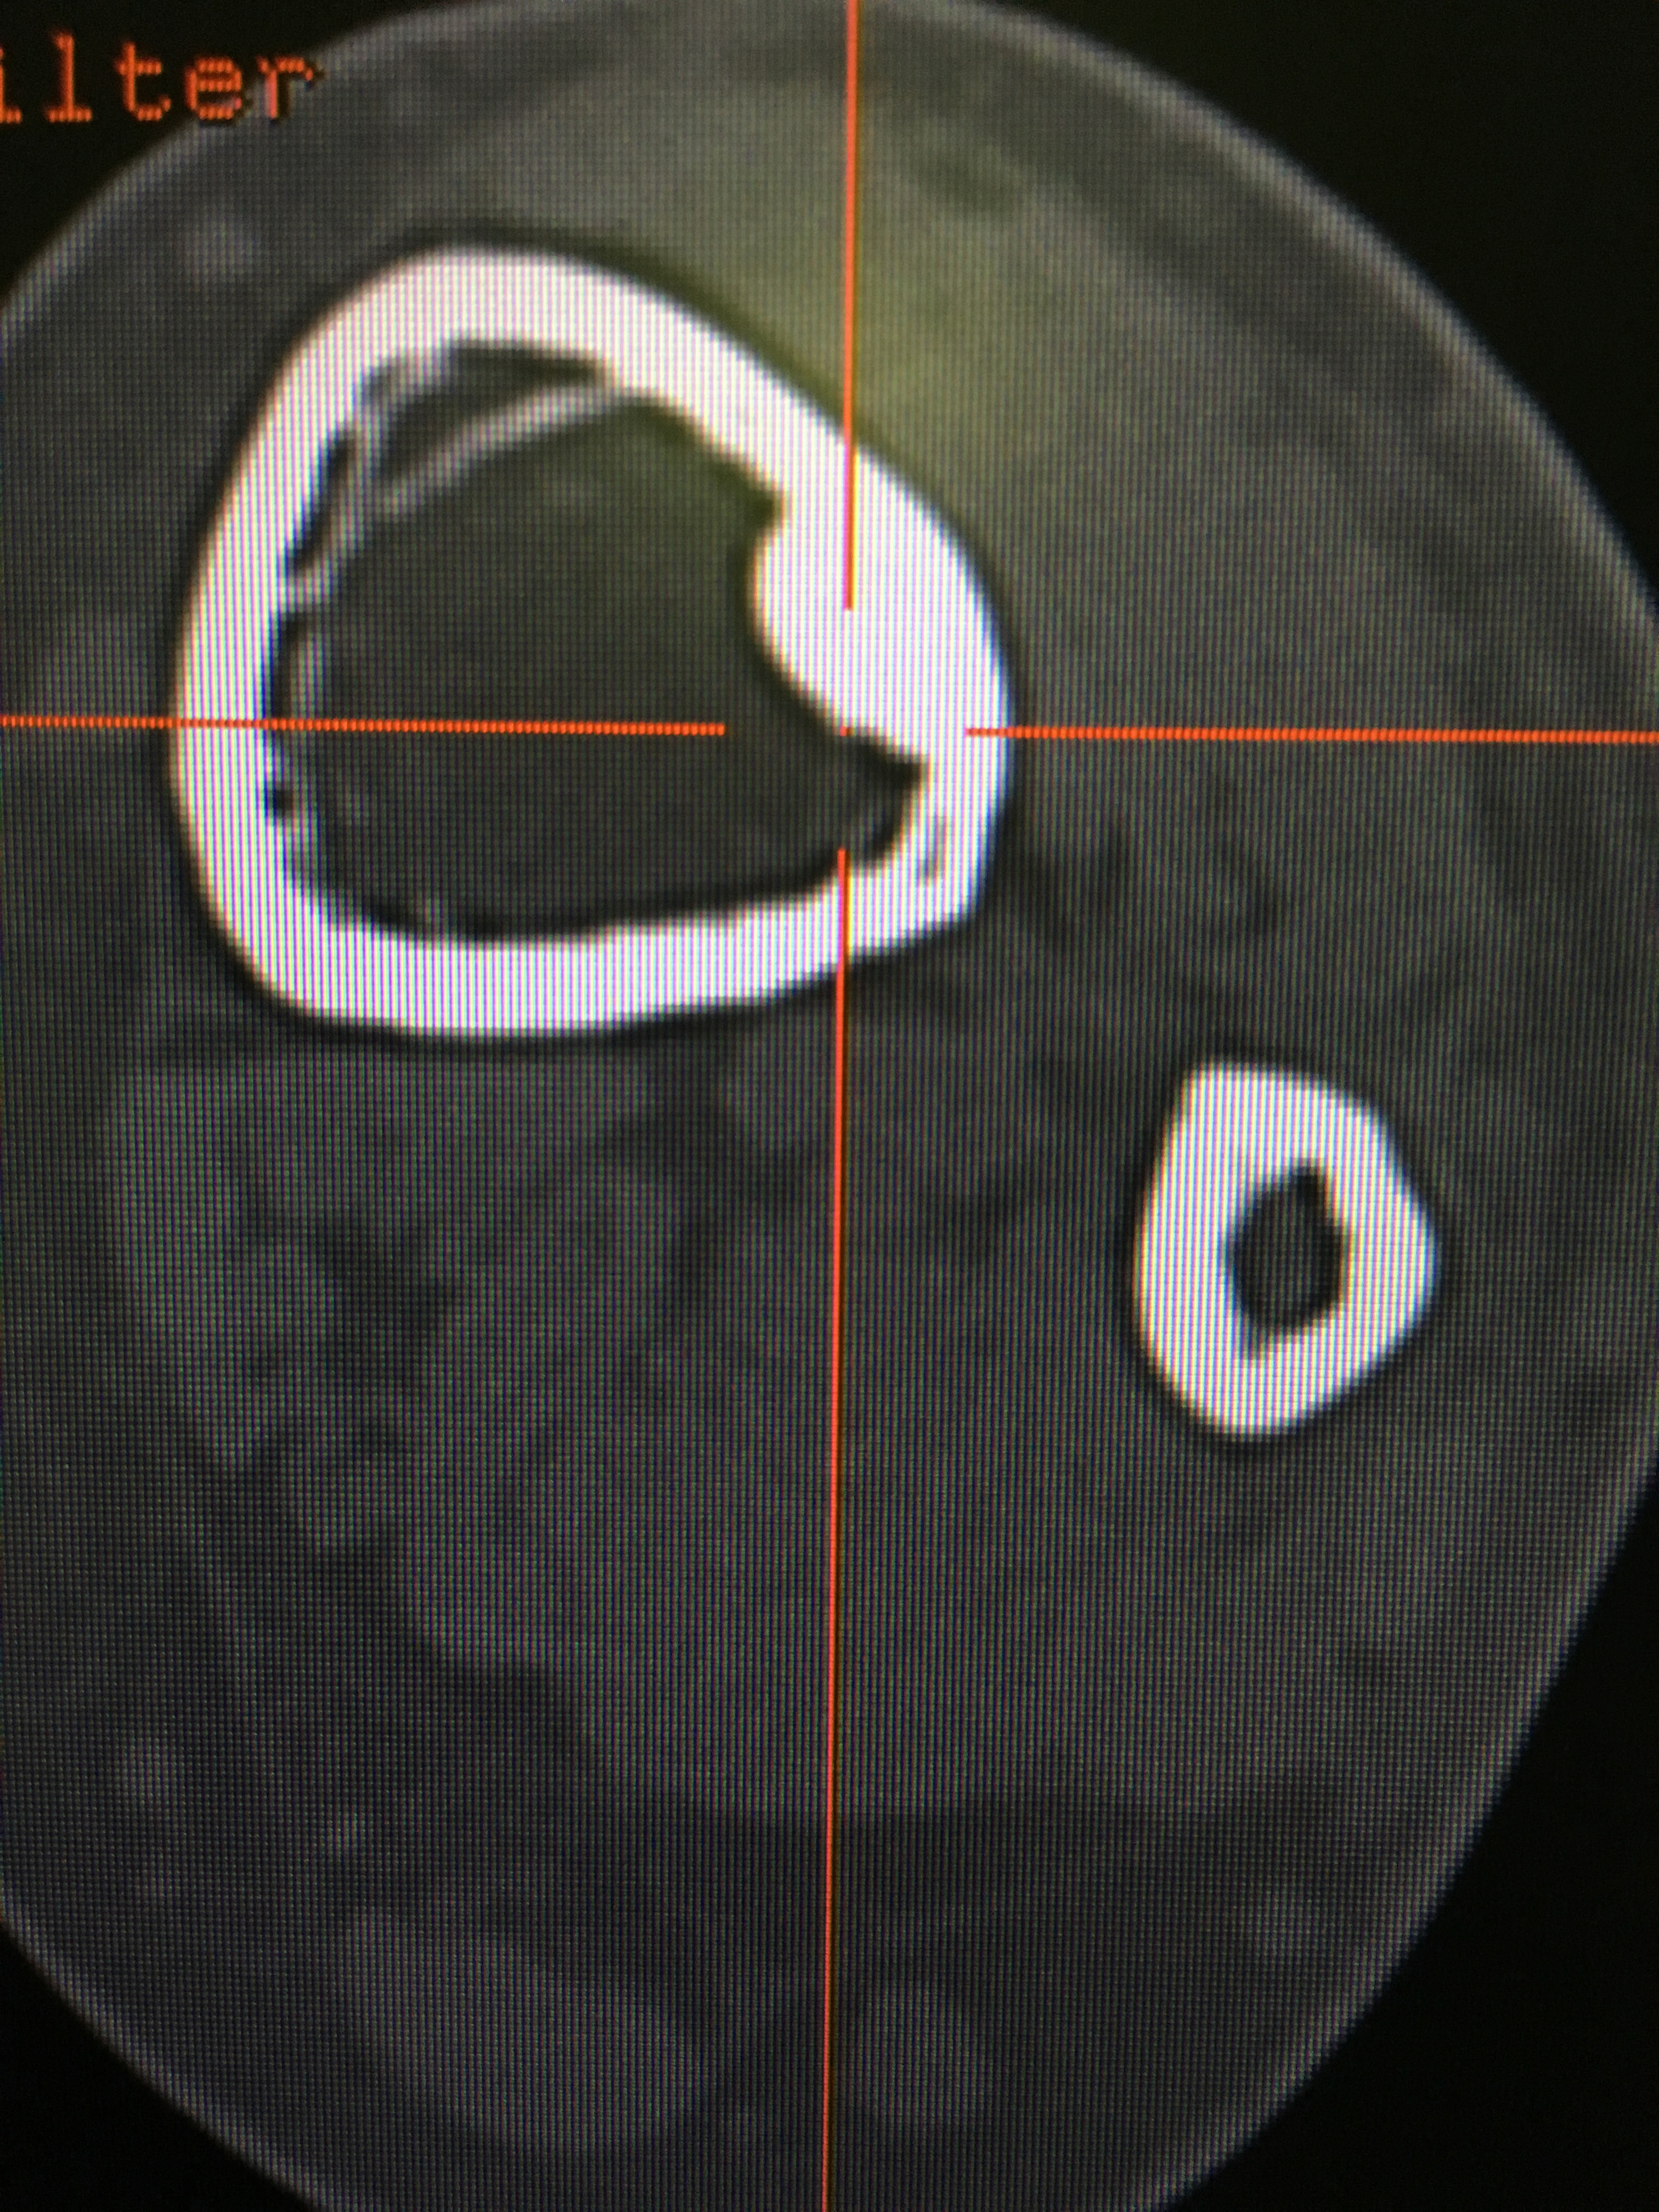

Coronal view bakshiortho.com